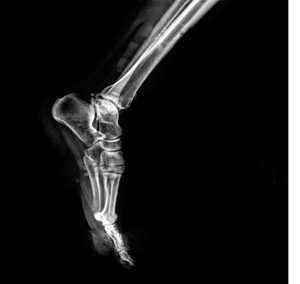

Информативность снимка. На снимке стопы в боковой проекции хорошо видны кости предплюсны: пяточная, таранная, ладьевидная, кубовидная и клиновидная. Кости плюсны проекционно наслаиваются друг на друга. Из всех костей наиболее отчетливо видна V плюсневая кость (рис. 446). На снимках стопы могут быть выявлены различные травматические, воспалительные и опухолевые поражения костей.

Информативность снимков. На рентгенограммах пяточной кости в боковой проекции выявляются структура и контуры пяточной и таранной костей (рис. 453).